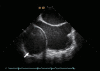

We present a case of successful surgical resection of a giant left ventricular (LV) pseudoaneurysm that developed 5 yr after mitral valve replacement (MVR). A 59-yr-old female was admitted with exertional chest pain radiating to left arm and back. 64-slice multidetector computed tomography (MDCT) revealed significant stenosis on the ostium of the first diagonal branch of the left anterior descending coronary artery and also a huge pseudoaneurysm compressing the right atrium and the inferior vena cava. She underwent resection of the pseudoaneurysm, and the pseudoaneurysm tunnel was repaired from the inside of LV cavity by removing the previously inserted prosthetic valve, followed by redo MVR together with coronary arterial bypass grafting (CABG) for a single-vessel disease. At the 6-month follow-up, the patient continued to do well without any complications.